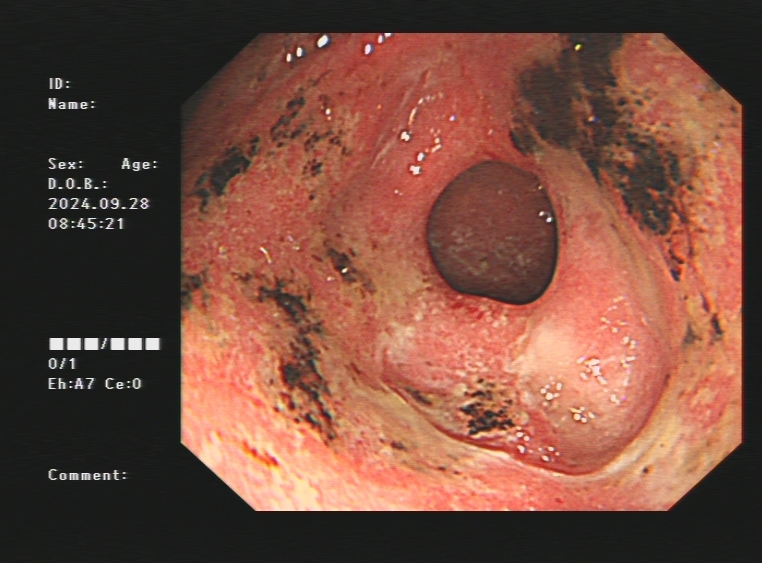

1.上消化道出血常见原因:消化性溃疡(胃溃疡、十二指肠溃疡)、食管炎、急性糜烂出血性胃炎、上消化道肿瘤(食管癌、胃癌)、剧烈呕吐造成的食管贲门黏膜撕裂伤、肝硬化引起的食管胃底静脉曲张。以下是一些常见的上消化道出血内镜图片:

急性胃黏膜病变出血、十二指肠球部溃疡出血及镜下止血夹止血